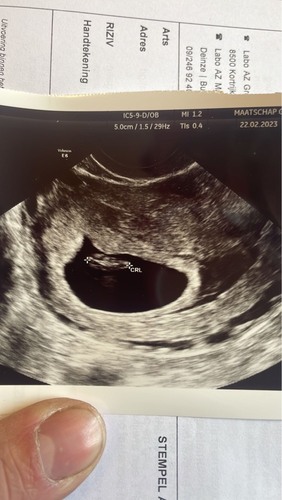

Volgens de ramzi krijgen wij een meisje, ik zal het laten weten na de uitslag van de nipt test 😉 is wel pas 13 april. Dus vermoedelijk kan ik dat hier posten rond 20 april

Jou baby ligt meer aan de linker kant. En het in inwendig, dan krijg je volgens deze theorie een meisje